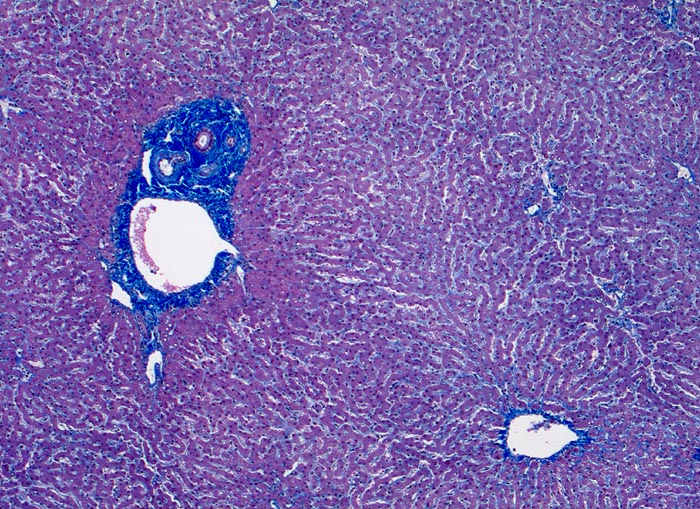

Normales Leberparenchym mit Portalfeld und Zentralvene

Links im Bild ein Portalfeld mit Portalvenenast, Arterienast und Gallengang. Das Portalfeld zeigt eine minimale Fibrose. Keine Entzündugnsinfiltrate. Rechts unten im Bild ein Zentralvenenast. Das Parenchym zeigt keine Verfettung und keine Entzündungsinfiltrate. Die Sinusoide sind nicht dilatiert.